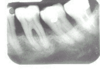

- Petit à petit, et parfois sans signe visible ni douleur, l'os soutenant les dents est détruit sous l'effet des parasites et des bactéries, créant ainsi une poche dans laquelle du tartre s'accumule, entretenant l'inflammation et empechant la gencive de se recoller à la racine.

- L'os diminuant progressivement, le déchaussement s'accentue, les dents deviennent de plus en plus mobiles allant jusqu'à tomber.